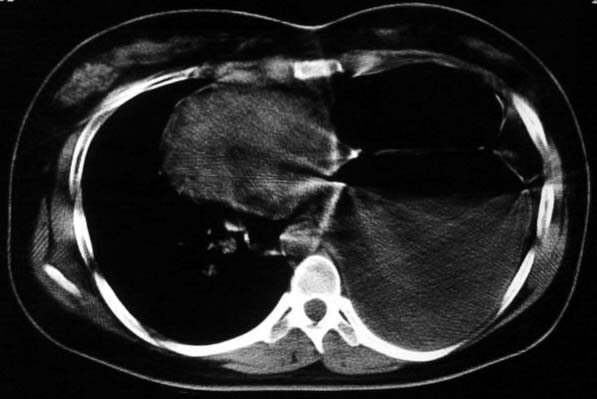

标题: CT5517:女性、24岁,反复胸痛、气促不能平卧半月。 [打印本页]

标题: CT5517:女性、24岁,反复胸痛、气促不能平卧半月。

左侧气液腔与胃腔影相连,考虑膈疝。钡餐检查有助于诊断。

左侧气液腔与胃腔影相连,考虑膈疝。钡餐检查有助于诊断

左侧气液腔与胃腔影相连,考虑膈疝。口服urografin检查有助于诊断。

谨慎!喝钡透视一下吧。冒然报一液气胸,临床再穿刺引流结果把胃戳个大洞就麻烦了!